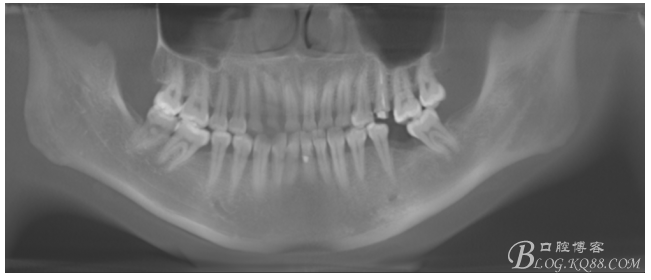

檢查:36.46缺失,36缺牙區(qū)近遠(yuǎn)中間隙約3mm,46缺牙區(qū)間隙約0.5mm,37.47.48近中傾斜,48近中面齲壞達(dá)牙本質(zhì)淺層,37牙周探診4mm,47近中探診深度5-6mm,不松,口內(nèi)照片及CT片如下:

術(shù)前CT